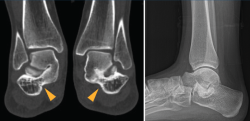

Figura 1. Segundo caso: coalición tarsal talocalcánea sinostótica bilateral. Pie derecho. Tomografía axial computarizada y radiografía.

Se trata de una de las causas más comunes del pie plano rígido doloroso en la población pediátrica(9,10,11). El dolor es el síntoma predominante(12,13,14) y de consulta, especialmente tras la actividad física. Los esguinces de repetición, desaxaciones, pies planos y contracturas de peroneos son también formas de presentación habituales (Figura 2). Llegaremos al diagnóstico de dicha patología por sospecha clínica y radiológica, y confirmación por tomografía axial computarizada (TAC) y eventualmente resonancia magnética nuclear (RMN)(15)(Figura 3).

Figura 3. Confirmación de la coalición por resonancia magnética nuclear y tomografía axial computarizada.